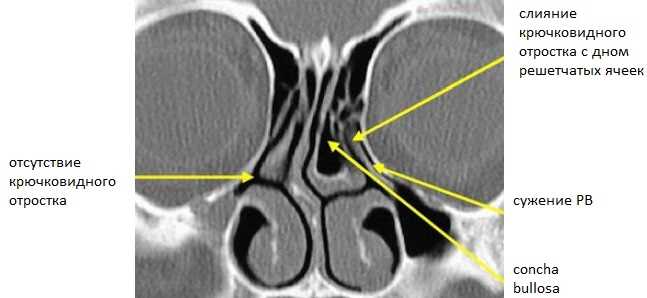

Общая характеристика симптомов и причин буллезной трансформации средней носовой раковины справа

В данном разделе рассмотрены основные проявления и возможные факторы возникновения буллезной трансформации средней носовой раковины справа. Симптомы данного заболевания могут выражаться в различных проявлениях, таких как нарушение носового дыхания, неприятные ощущения в области носовой полости, а также появление отдельных выделений из носа.

Причины развития буллезной трансформации средней носовой раковины справа могут быть связаны с различными факторами. Среди них могут быть генетическая предрасположенность к данному заболеванию, хронические заболевания верхних дыхательных путей, воздействие вредных привычек, а также травмы и другие воздействия на носовую полость.

Основной задачей в диагностике данного заболевания является выявление специфических изменений в правой полости носа, что позволит точно определить патологический процесс. В процессе диагностики врач может использовать такие методы, как клинический осмотр, анамнез, лабораторные и инструментальные исследования. Клинический осмотр позволяет выявить видимые изменения в носовой полости, такие как отечность, кровотечение или наличие опухоли.

Для более точной диагностики и определения масштабов заболевания могут применяться лабораторные и инструментальные исследования, такие как рентгенография, компьютерная томография, риноскопия и магнитно-резонансная томография. Проведение этих исследований позволяет получить дополнительную информацию о состоянии правой полости носа и определить требуемые тактики лечения.